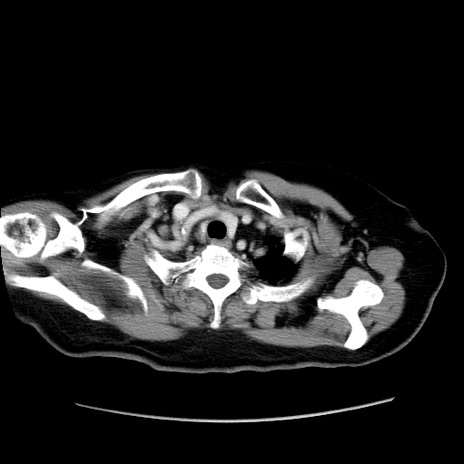

冠状断像

【症例】80歳代女性

【主訴】下腹部痛

【現病歴】約8時間前より下腹部痛の出現あり、救急外来受診。

【既往歴】両側付属器切除

【身体所見】意識清明、下腹部正中に手術痕あり、その部位に一致して圧痛と反跳痛あり。腸蠕動音は亢進。

【データ】WBC 9300、CRP 0.15